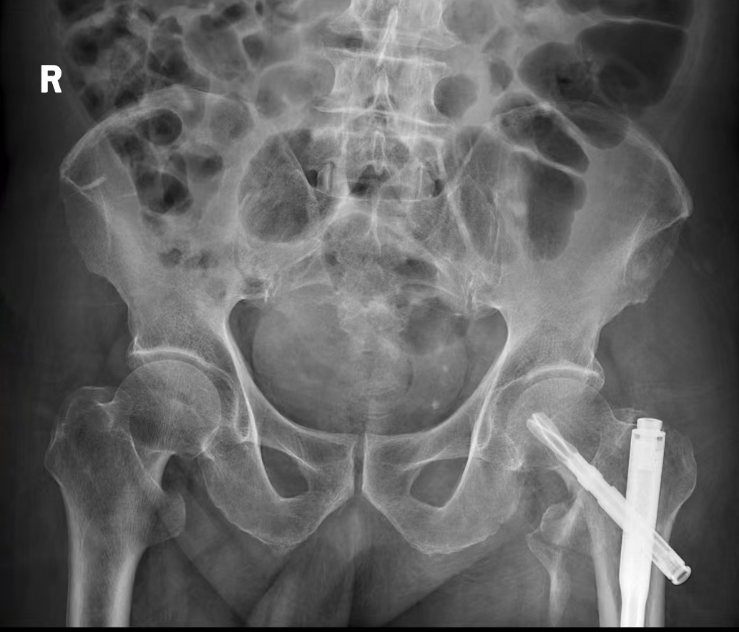

手术切口和术后图片(右图红色线条示意微创手术切口)

患者和家属同意手术后,在医院多学科努力下,克服患者长期口服氯吡格雷等抗凝药物等困难,在伤后2天内通过髂筋膜阻滞复合麻醉和微创手术的方法,为患者实施了骨折闭合复位髓内针内固定手术,手术仅有两个长为3cm的切口,出血约为50ml。术后通过ICU病房监护调整,手术次日患者即转入普通病房并开始在保护下站立负重训练,摆脱了卧床状态。既往这种高风险高龄患者常需调整5-7天后方能手术,术后由于心肺功能和肌力的下降,康复效果也要打一个大的折扣。为改善预后,提高疗效,阳新县人民医院积极响应国家卫健委号召,推动开展老年髋部骨折的多学科诊疗工作,促进老年患者的加速康复,肖大爷是其中一个典型示例。

术后肖爷爷精神状态良好,第二天即在医务人员的指导下进行床旁的坐立等康复训练,肖爷爷看到小小的手术切口直称“神奇”,家属更是对医护人员感激不已,也道出了心里话。“其实之前我们也曾想到外地的大医院去治疗的,后面了解到连云港的骨科教授在阳新人民医院帮扶带教,所以才决定留下来住院治疗的,可真没有想到手术这么成功而且恢复的这么快。”